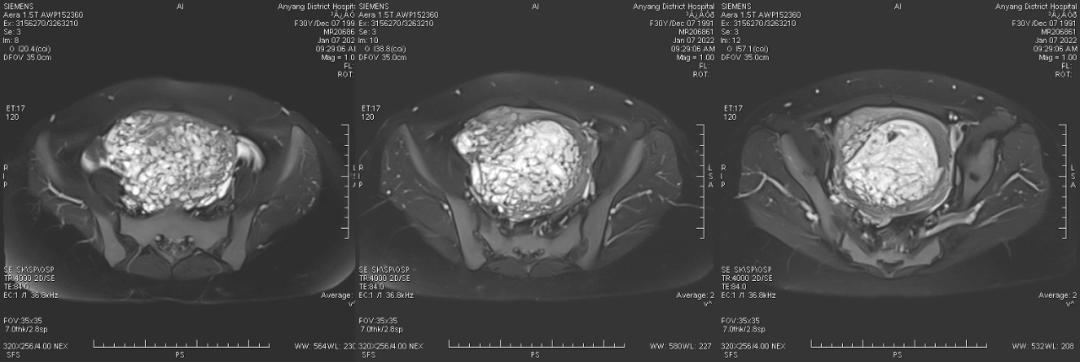

病例一

女,18 岁,孕 19 周 6 天,妊娠合并胎盘部分性葡萄胎 1 月余,病灶与子宫肌层分界清晰。

孕早 期因胃痛曾应用氨苄西林粉、西咪替丁、维生素 B6、山莨菪碱、胃炎颗粒、胃灵颗粒、吗丁啉对症治 疗。 外院彩超提示: 宫内妊娠,单活胎,胎儿室间隔缺损,胎盘 下方见异常不均质回声,范围约 109*41*108 mm,内呈蜂窝状改变,与胎盘分界不清,考虑部分性葡萄胎可能,建议终止妊娠。 为进一步终止妊娠就诊我院。